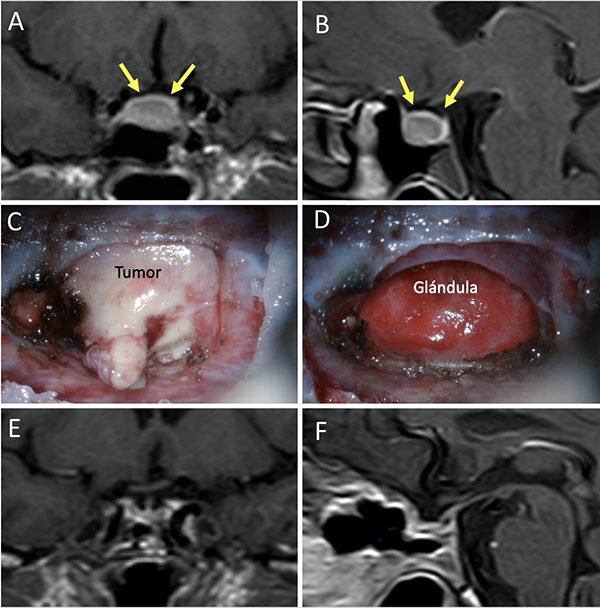

Una clasificación clásica de los adenomas es según su tamaño. Se los clasifica en microadenoma <10 mm (fig. 2), macroadenoma >10 mm (fig. 3), y adenoma gigante > 30 mm (fig. 4). Esta clasificación es importante ya que los índices de remisión están ligados al tamaño del adenoma y también su recidiva.12

Figura 2: Microadenoma. A-B: RM preoperatoria; C-D: RM postoperatoria.

El techo de la fosa pituitaria está constituido en condiciones normales por un máximo de 2 estructuras: duramadre (diafragma selar) y aracnoides.65,66 En condiciones patológicas, cuando existe un adenoma hipofisario, éste empuja hacia arriba a la glándula. De este modo, la interfase entre el tumor y el LCR se encuentra constituida por un máximo de 3 elementos: glándula, duramadre y aracnoides. Cabe destacar que la aracnoides es el único elemento constante. A los elementos que constituyen esta interfase el equipo de Tucumán los denominó “barrera selar”.11,60

Existen 3 subtipos de barrera selar según los hallazgos intraoperatorios, luego de resecar el tumor:

Un factor interesante de este novedoso concepto es que el tipo de barrera puede evidenciarse en la RM preoperatoria. De este modo, existen 3 subtipos de barrera selar según la radiología:

Los pacientes con una barrera débil tienen mayor riesgo de fístula intraoperatoria de LCR. La barrera fuerte es un factor protector de fístula de LCR.11,60

Figura 6: Barrera selar fuerte. A-B) RM preoperatoria. C-D) Hallazgos intraquirúrgicos. E-F) RM postoperatoria. Flechas amarillas: interlinea > 1mm. Tomado de Campero A, Villalonga JF, Basso A. Anatomical risk factors for intraoperative cerebrospinal fluid leaks during transsphenoidal surgery for pituitary adenomas. World Neurosurg. 2019;124:346-55.